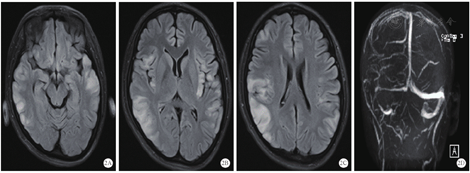

患者不能完全排除自身免疫性脑炎,转入ICU后,给予阿昔洛韦抗病毒、甘露醇脱水降颅压、乙酰谷酰胺营养脑细胞、静脉注射人免疫球蛋白和甲泼尼龙琥珀酸钠调节免疫、丙戊酸钠和左乙拉西坦控制癫痫等综合治疗。入院第4天,患者心率偏慢,最慢为40次/min左右,考虑存在自主神经功能紊乱,给予心宝丸及环磷腺苷葡胺提升心率;约4 d后心率逐渐恢复至75~120次/min,停用心宝丸和环磷腺苷葡胺。入ICU后仍间断出现癫痫发作,加用拉莫三嗪和苯巴比妥控制癫痫发作。入院第7天,患者血清及脑脊液自身免疫性脑炎相关抗体检测为阴性,脑脊液病原微生物基因组检测提示:猫立克次体感染(检出序列数261)。考虑患者存在立克次体感染可能,停用甲泼尼龙琥珀酸钠,给予盐酸米诺环素胶囊及甲磺酸左氧氟沙星氯化钠抗感染。入院第10天,患者间断出现呼吸暂停,伴有血氧饱和度下降,给予经口气管插管,呼吸机辅助呼吸。入院第12天,复查颅脑CT未见明显异常(图1A);胸部CT显示双肺多发高密度影,右肺上下叶部分支气管欠通畅,考虑感染性病变(图1B)。考虑患者肺部感染较重,给予头孢哌酮舒巴坦钠抗感染。入院第14天,复查脑脊液为无色清亮液体,压力约为217.6 mmH2O;脑脊液常规、蛋白未见明显异常。入院第15天和第16天,分别组织全院病例讨论及解放军总医院远程会诊,主要诊断考虑癫痫持续状态(难治性)、重症脑炎,脑炎性质考虑立克次体感染,不除外病毒感染,继续抗立克次体、抗病毒、丙种球蛋白抑制免疫反应、控制癫痫发作等治疗。入院第22天,第二次腰穿送检脑脊液病原微生物基因检测未再检测出猫立克次体。于当日复查颅脑CT显示双侧颞顶叶多发条片状稍低密度影,提示有脑炎可能(图1C);胸部CT显示双肺多发高密度影,右肺下叶部分支气管欠通畅,提示较前明显好转(图1D)。继续给予阿昔洛韦抗病毒,米诺环素及甲磺酸左氧氟沙星氯化钠抗立克次体治疗。入院第23天,拔除气管导管,患者呼吸平稳。入院第25天,患者出现皮疹,皮肤科会诊考虑:过敏性皮炎,重症多形性红斑?(药物引起可能性大)。给予甲泼尼松龙琥珀酸钠注射液60 mg静脉滴注,再次给予人免疫球蛋白0.4 g·kg-1·d-1静脉滴注,连用5 d。入院第27天起,患者的意识逐渐转清,可下床活动,能够配合指令完成动作,未再出现肢体抽搐。入院第32天,第3轮丙种球蛋白治疗结束,当日完善颅脑磁共振成像(magnetic resonance imaging,MRI)检查显示双侧额顶颞岛叶异常信号,考虑炎症,建议治疗后复查;右侧横窦、乙状窦较对侧纤细,考虑发育变异(图2)。入院第33天,患者转回普通病房,意识清,无头痛,无发热,颜面部及颈前皮疹较前减轻,四肢活动基本正常。入院第46天,患者好转出院,出院时意识清,问话对答切题,未见新发皮疹,四肢肌力5级,双侧巴宾斯基征阴性。出院4个月后,患者再次出现癫痫发作,复查颅脑MRI显示双侧额顶颞岛叶异常信号基本吸收、消失,脑部MRI增强未见异常强化(图3)。继续口服左乙拉西坦片,未再出现癫痫发作。